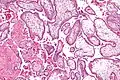

Micrografía que muestra vellosidades coriónicas. Ampliación muy alta. Tinción H&E. -